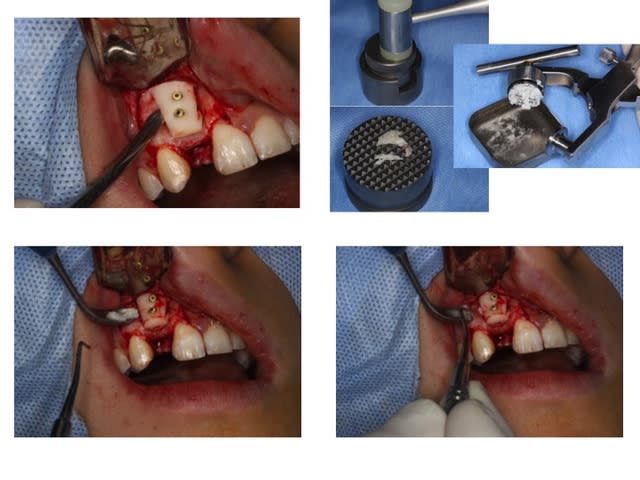

Greffe 2D:

Greffon mince en vestibulaire qui coulisse sur les deux vis, on écarte du SR ( photo avec syndesmotome faucille) on glisse dessous les fragments copeaux d'os et on ressert un peu à la fin

Donc le greffon cortical sert de membrane pour protéger le lit de copeaux

Le photos sont dans l'ordre de réalisation

Prélèvement rétromolaire/ramique

Nettoyage du SR avec fraise boule pour retirer tout les tissus fibreux sur l'os et accessoirement ouvrir les espaces médullaire ( en théorie ) Ici grosse frayeur car l'apex de 11 est dans le vide ainsi que la moitié de la dent: toute la face vestibulaire et distal... Merci Mrs les ortho.....

Séparation du greffon en deux et mise en forme

Préparation des trous de vis en diam 1,5 pour vis de 1,3 et cuvette pour les têtes de vis

Pince de barth pour maintenir le greffon et forage dans les trous au forêt de 1mm et mise en place des vis. Le greffon est libre, pour pouvoir régler l'épaisseur souhaitée.

Broyage du reste du prélèvement

Le greffon est soulevé pour glisser dessous le broyât osseux

Serrage final des vis et élimination des angles tranchants à la fraise boule diamantée